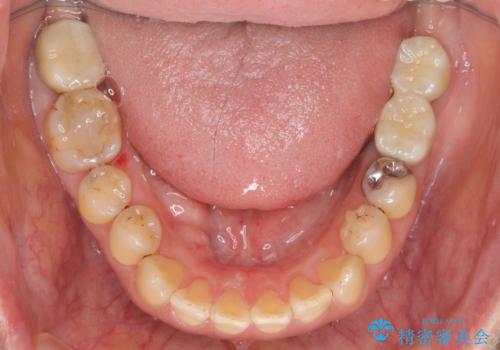

歯周病に対する全体治療

治療期間はかかりましたが、しっかりと歯周病治療・インプラント治療を行ったおかげで歯周病の状態は非常に良くなり、安定した咬合関係を確立することができました。